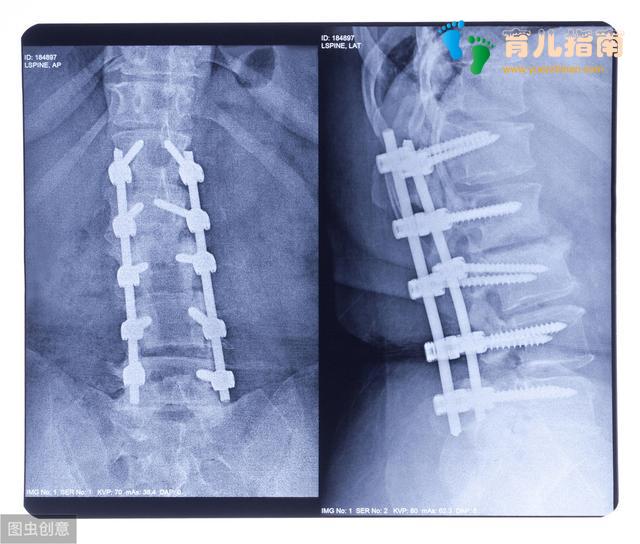

而上文家长关心的脊柱侧弯问题,我也要讲一下,首先要讲一下脊柱侧弯是什么,简单说脊柱侧弯是指脊柱发生弯曲,是一种脊柱结构性的侧弯,原因有很多,有的是先天性的也有后天形成的,临床上女孩比男孩多见。一般发生在初中或高中的孩子身上的脊柱侧弯考虑特发性脊柱侧弯,意思是原因不明确,典型症状是双肩高低不平,脊柱偏离中线,肩胛骨一高一低,一侧胸部出现皱褶皮纹,前弯时双侧背部不对称。当孩子一侧肩胛似乎比另一侧高时,或衣服不能拉直时要首先怀疑到有脊柱侧弯,但更多的是在体格检查中查出的,最早的表现可能是久坐或站后出现腰部无力等。脊柱侧弯10度及以上就需要到医院专业的骨科医生那里就诊,根据发现时的年龄和弯曲的程度或类型,治疗可分为观察、支具矫正或手术治疗。